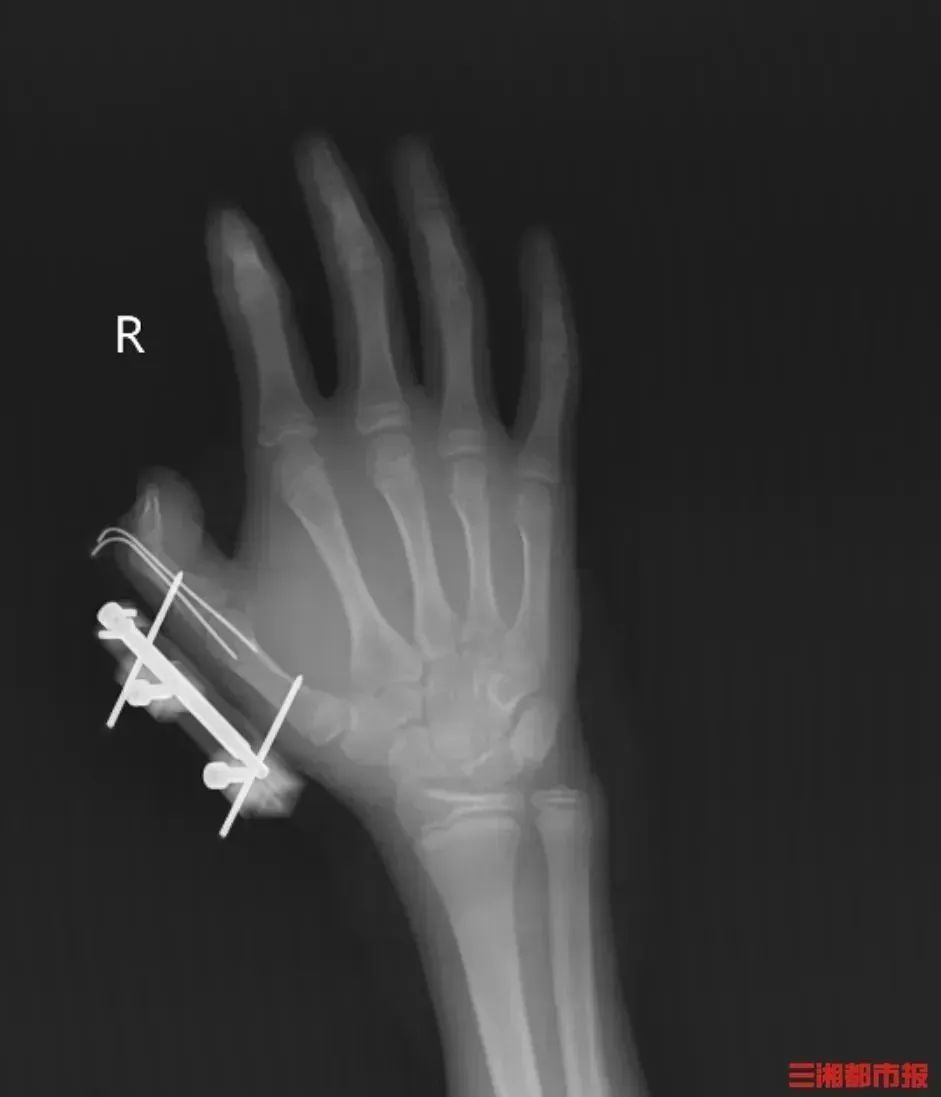

突然,密封袋里的干冰发生爆炸,维维的右手瞬间鲜血直流,拇指虎口处被撕开一道约10厘米的伤口,深可见骨,肌肉组织断裂外露,还伴随着拇指骨折、关节脱位,整个拇指完全失去知觉。

图源:三湘都市报

见状,家人赶紧带他到当地医院包扎,随后紧急转往湖南省人民医院手足显微外科。经治疗,维维的拇指保住了,但后续还需长期康复训练,才能慢慢恢复手部精细动作功能。